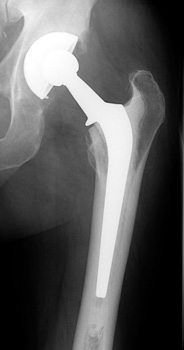

• Hybrid (only femoral component cemented)

Hybrid (only femoral component cemented)